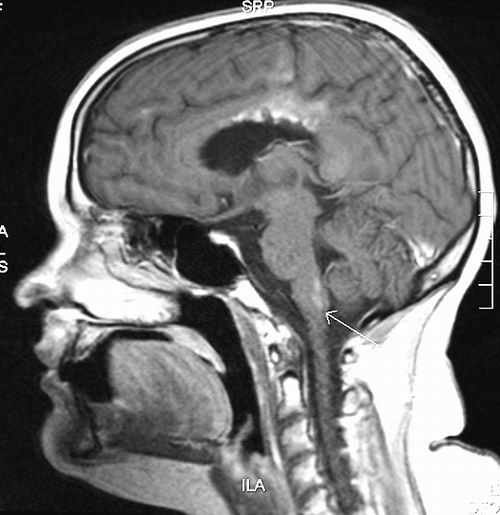

最新的磁共振成像研究使人们进一步了解脑部疾病。图片来源:英国诺丁汉大学

磁共振成像(MRI)领域的一项新发现有望提高多发性硬化症等脑部疾病的诊断率和监测效果。研究人员指出,来自英国诺丁汉大学彼得·曼斯菲尔德爵士磁共振中心的这一研究成果,可能会为医学界的磁共振成像提供一种新工具。

该项研究发表在日前出版的美国《国家科学院院刊》上,它揭示了利用新的磁共振成像技术生成的脑部图像为何对神经纤维走向如此敏感。